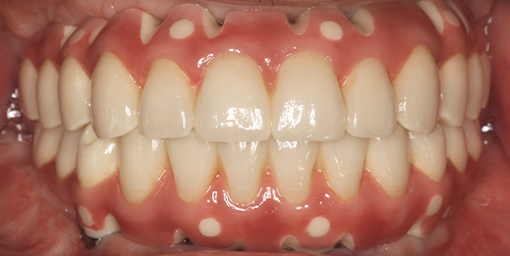

旅行や食事を楽しめるように歯を治したい 【オールオン4・オールオン6】